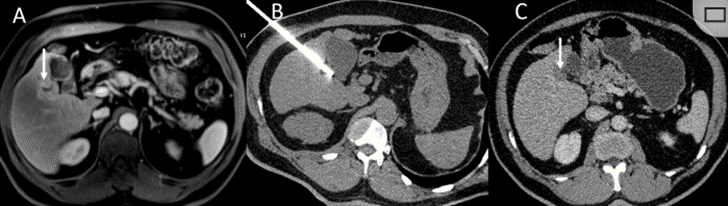

冷凍消融膽囊附近腫瘤病灶

(A)動(dòng)脈期 MRI 顯示膽囊附近有外周增強(qiáng)病變(箭頭)。

(B)手術(shù)過程中 CT 顯示冷凍探針位于病灶內(nèi)。

(C)消融后,術(shù)后 1 個(gè)月CT 顯示完全消融(箭頭)。